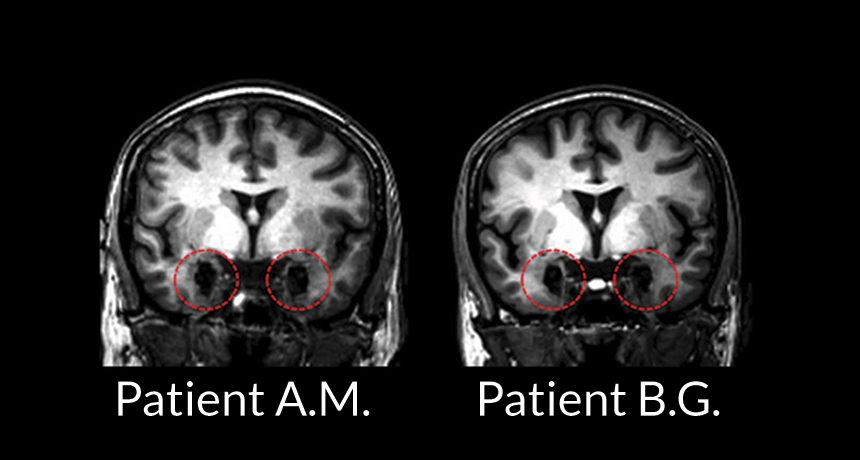

FEAR FACTORS  Despite extensive damage in their amygdalae (red circles in these MRI scans), twin sisters A.M. and B.G. still can experience anxiety prompted by bodily cues, a new study shows.

In a pair of twin sisters, a rare disease had damaged the brain’s structures believed necessary to feel fear.